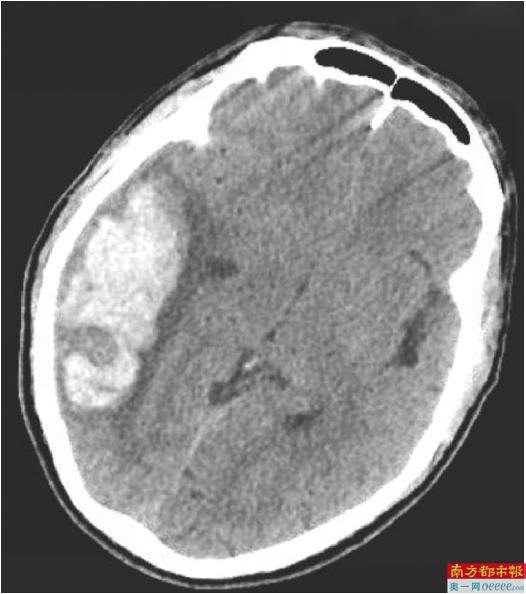

患者术前影像。 通讯员供图

南科大医院神经外科主任鲁春鹤介绍,患者当时右侧顶枕颞叶脑出血量高达约40mL,右侧大脑半球脑水肿、大脑镰下疝接踵而至,生命体征急速恶化,大脑里破裂的血管如同随时可能引爆的“定时炸弹”,情况岌岌可危。

危急时刻,医院神经外科手术团队火速响应,启动急救绿色通道。鲁春鹤带领团队,化身“拆弹专家”,凭借精湛的医术和丰富的经验,在复杂的脑血管结构中“抽丝剥茧”,精准定位畸形血管团。手术完整切除畸形血管团、彻底清除血肿,成功为患者拆除致命“炸弹”。术后24小时,患者清醒,各项生命体征逐渐平稳。